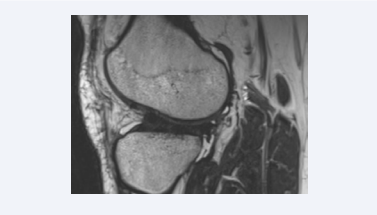

The normal ACL appears as an obliquely oriented, taut, continuous fibrous band extending from the posteromedial aspect of the lateral femoral condyle to the anterior aspect of the tibial eminence (Figure 1A).

Imaging appearance of normal ACL. (A) The normal ACL appears taut with a slope slightly more vertical to the Blumensaat line. The ACL exhibits a striated  appearance with alternating bands of low and intermediate signal intensity. (B) Oblique coronal image that parallels the course of the ACL show the anteromedial and  posterolateral bundle, which are named based on the relative insertion sites on the tibia.

Figure 1: Imaging appearance of normal ACL. (A) The normal ACL appears taut with a slope slightly more vertical to the Blumensaat line. The ACL exhibits a striated appearance with alternating bands of low and intermediate signal intensity. (B) Oblique coronal image that parallels the course of the ACL show the anteromedial and posterolateral bundle, which are named based on the relative insertion sites on the tibia.

The slope of the ACL should be parallel or near parallel to the roof of the intercondylar notch (Blumensaat line). The proximal portion of the ACL exhibits an oval-shape in cross-section with uniform low-signal intensity on T1-, intermediate- and T2-weighted pulse sequences. As the ACL approaches the tibial insertion, the fibers are flared, and the signal intensity is increased exhibiting a striated appearance with alternating bands of low and intermediate signal intensity. The AM and PL bundles can be distinguished with intermediate signal intensity interposed between the two bundles (Figure 1B).